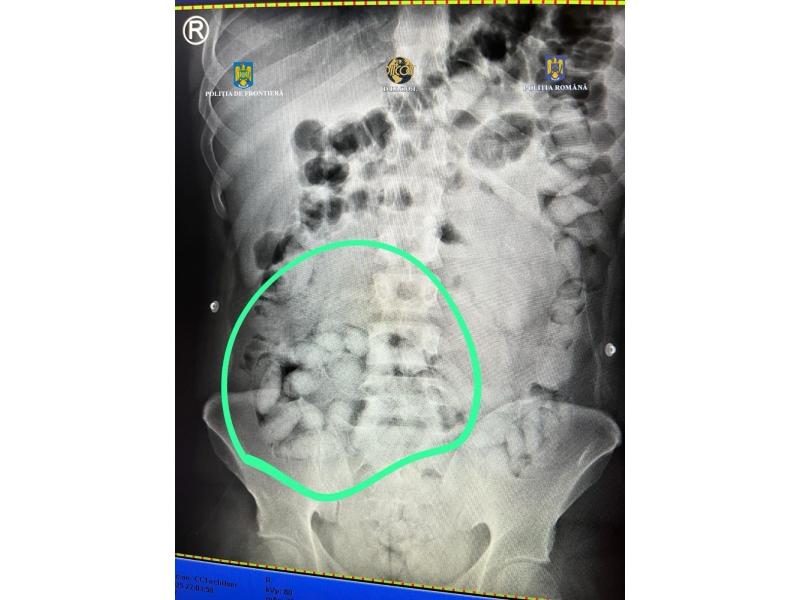

În urma controlului efectuat cu ajutorul unui scaner cu raze X, în interiorul abdomenului bărbatului au fost observate mai multe formațiuni neobișnuite, care nu corespund anatomiei umane.

Acesta a fost condus la o unitate spitalicească, unde, pe parcursul internării, ar fi eliminat 62 de cașete, ce conțineau aproximativ 350 de grame de substanță pulverulentă (în prezent aflată în curs de expertizare).